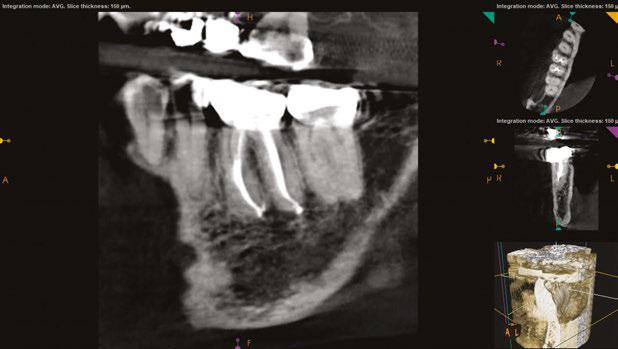

USA, Savannah, Georgia) and gutta percha via continuous wave condensation. EndoSequence BC liner blue (Brasseler USA, Savannah, Georgia) was placed over the gutta percha at the canal orifice, and the tooth was temporized using a cotton pellet and Fuji IX placed in the access (Figure 6). Following completion of the root canal, the patient was scheduled for a 3-month reevaluation and referred to her provider for definitive restoration. Healing was observed at the 3- and 6-month postoperative visits. Periapical radiographs were exposed at each visit revealing bony healing (Figure 7). The patient reported no pain or symptoms following nonsurgical root canal treatment. At both visits, percussion and palpation were negative. A CBCT was captured at the 6-month postoperative exam to evaluate healing. Coronal CBCT slices revealed a reduction in lesion size to 3.5 mm x 1.6 mm. Sagittal slices also showed reduction in lesion and maintained health of bone surrounding implant No. 12 (Figure 8). A 2011 article by Ng outlines eleven factors that, if present, improve periapical healing following primary non-surgical root canal treatment.17 Only two of these eleven factors, absence of a preoperative periapical lesion and size of the preoperative periapical lesion, were not met in this case report. Along with this and the 2017 AAE Treatment Options for the Compromised Tooth: A Decision Guide article, the final prognosis for healing is favorable.16

Figures 8A-8B: CBCT was taken at the 6-month postoperative visit. 8A. Coronal CBCT slices revealed a reduction in lesion size to 3.5 mm x 1.6 mm. 8B. Sagittal CBCT slices revealed a reduction in lesion size and maintained health of bone surrounding implant No. 12